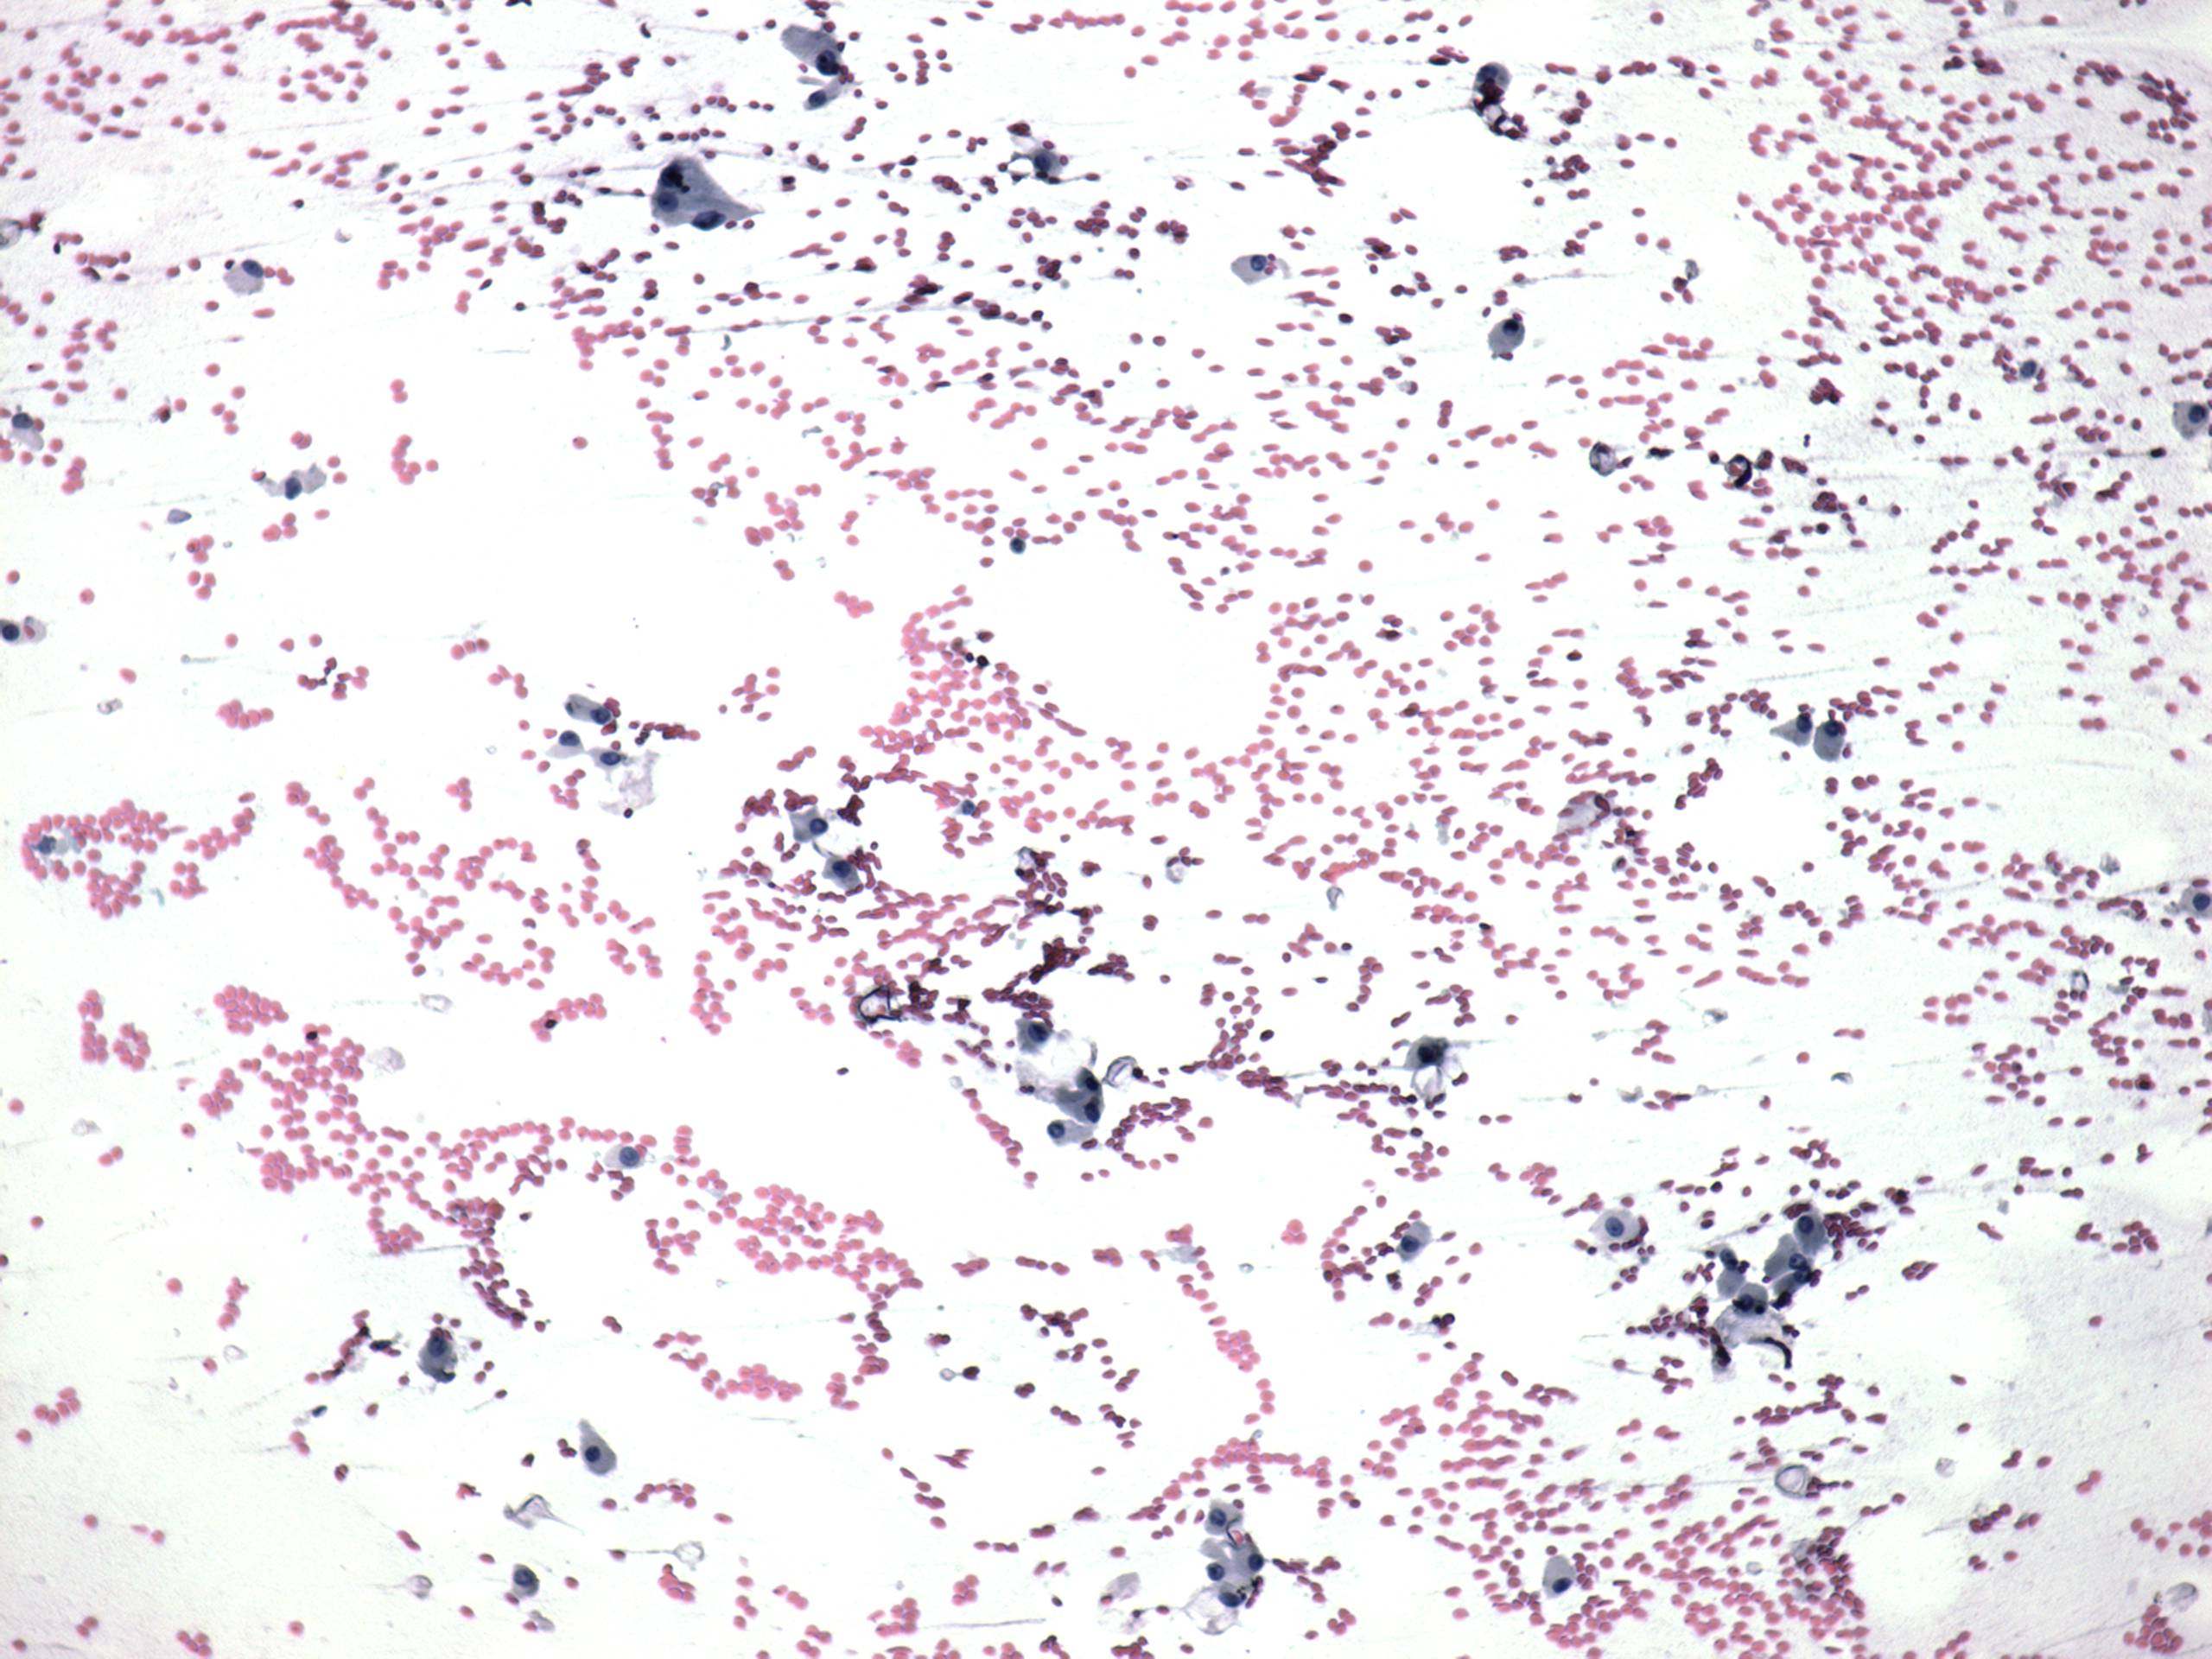

Follicular carcinoma - Case 6. (cytologic picture 1)

Pap-smear, 100x. Follicular cells dispersed and forming microfollicles.